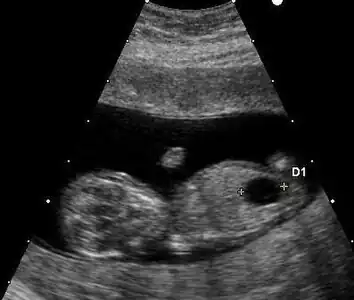

Ultrazvuk

Ke screeningu Downova syndromu lze použít ultrazvukové vyšetření. Mezi nálezy, které ukazují na zvýšené riziko, pokud jsou pozorovány ve 14. až 24. týdnu těhotenství, patří mimo jiné malá nebo žádná nosní kůstka, velké srdeční komory, tloušťka nuchální řasy a abnormální pravá podklíčková tepna.[99] Přítomnost nebo nepřítomnost mnoha markerů je proto přesnější.[100] Zvýšená nuchální translucence (NT) plodu ukazuje na zvýšené riziko Downova syndromu, přičemž zachycuje 75–80 % případů a v 6 % je falešně pozitivní.[101]

Ultrazvuk plodu s Downovým syndromem ukazující velký močový měchýř

Zvýšená NT a chybějící nosní kůstka u plodu v 11. týdnu s Downovým syndromem